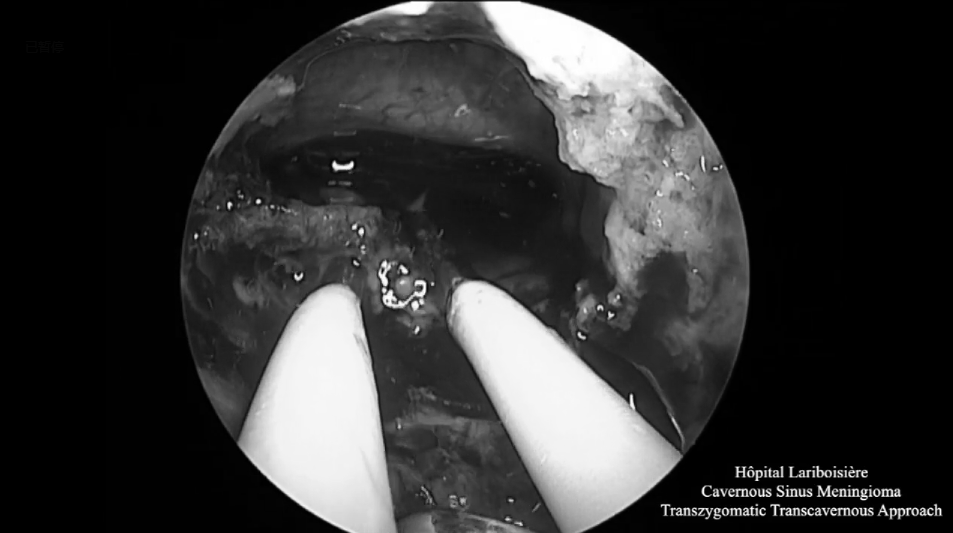

▼利用OPC间隙(orbitopterygopalatine corridor)进入蝶窦,发现肿瘤突出到窦内,暴露V2神经的侧面。神经内镜下对蝶窦中的肿瘤进行切除,这种方法可以切除硬膜内间隙和鼻窦中的肿瘤。为保留关键神经功能,海绵窦内的肿瘤没有切除。

▼神经内镜操作下暴露和切除肿瘤